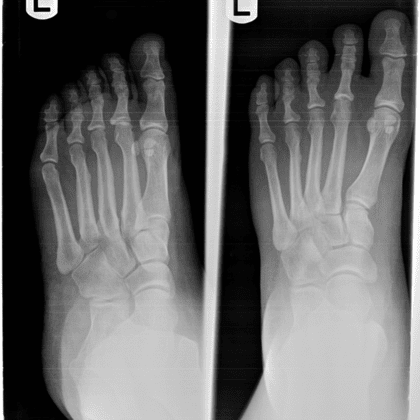

What Does Bone Cancer In The Foot Feel Like / What Does a Stress Fracture in The Foot Feel Like - Body ... - • may come and go or be constant.. The most common symptoms of the. Cancer in bone can cause intermittent or progressively severe localized bone pain where the cancer is in the bone. Limb pain and swelling are very common in normal, active children and teens. But it's important to get any symptoms checked out by your gp. Cancer can also spread to your bones from somewhere else.

Most cases of bone cancer develop in the long bones of the legs or upper arms. The bone pain is described as aching, throbbing, stabbing, and excruciating. Many people worry when they experience bone pain because it can be a sign of bone cancer. • bone pain from prostate cancer can feel like a dull ache or feel like a toothache in the bones, or you may feel a sharper sensation. Cancer can also spread to your bones from somewhere else.

Primary bone cancer is very rare. Cancer in bone can cause intermittent or progressively severe localized bone pain where the cancer is in the bone. Most cases of bone cancer develop in the long bones of the legs or upper arms. But it's important to get any symptoms checked out by your gp. Many people worry when they experience bone pain because it can be a sign of bone cancer. Limb pain and swelling are very common in normal, active children and teens. It can also be like an intermittent, sharp, and jabbing pain. Swelling in the area is another common symptom, although it might not occur until later. The bone pain is described as aching, throbbing, stabbing, and excruciating. The symptoms of bone cancer will vary, depending on the size of the cancer and where it is in the body. Cancer can also spread to your bones from somewhere else. • may come and go or be constant. The most common symptoms of the.

If you touch the affected area, you can probably feel a swelling, especially if the tumor occurs in bone without a lot of muscles around it, such as within the lower legs. The symptoms of bone cancer will vary, depending on the size of the cancer and where it is in the body. People may feel aches or pains in their bones for a variety of reasons. One of the most frequent symptoms associated with bone cancer is bone pain. But it's important to get any symptoms checked out by your gp.

• can worsen with movement. Pain from bone tumors can originate from within the bone. Depending on where the tumor is, it might be possible to feel a lump or mass. The affected leg or joint develops pain that is often described as consistent and dull, like a persistent ache. But it's important to get any symptoms checked out by your gp. Limb pain and swelling are very common in normal, active children and teens. The symptoms of bone cancer will vary, depending on the size of the cancer and where it is in the body. It can also be like an intermittent, sharp, and jabbing pain. • may come and go or be constant. Primary bone cancer is very rare. The most common symptoms of the. If you touch the affected area, you can probably feel a swelling, especially if the tumor occurs in bone without a lot of muscles around it, such as within the lower legs. This type of pain is usually characterized as burning, itching, or radiating.